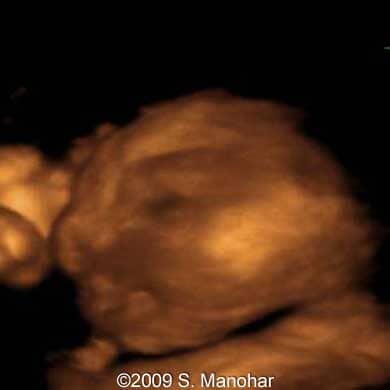

Images 14, 15, 16: 3D scans; the image 14 shows fetal face with the everted lips ("eclabion"); the image 15 shows fetal profile with absent ear; and the image 15 shows fetal face with eyelid edema and outward everted lower eyelid ("ectropion").

11

12

13